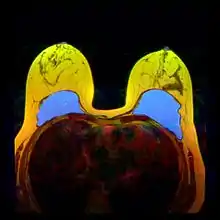

A breast implant is a prosthesis used to change the size, shape, and contour of a person's breast. In reconstructive plastic surgery, breast implants can be placed to restore a natural looking breast following a mastectomy, to correct congenital defects and deformities of the chest wall or, cosmetically, to enlarge the appearance of the breast through breast augmentation surgery.

In surgical practice, for the reconstruction of a breast, the tissue expander device is a temporary breast prosthesis used to form and establish an implant pocket for the future permanent breast implant. For the correction of male breast defects and deformities, the pectoral implant is the breast prosthesis used for the reconstruction and the aesthetic repair of a man's chest wall (see: gynecomastia and mastopexy).